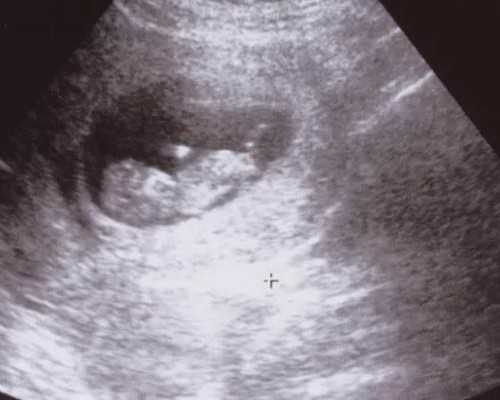

待卵泡完全发育成熟(至少有1~2个卵泡发育直径18㎜、2~3个17㎜),便安排注射破卵针,专家会在36小时后以B超引导+全麻的方式进行取卵,整个过程安全且无痛,仅需10分钟左右即可完成。